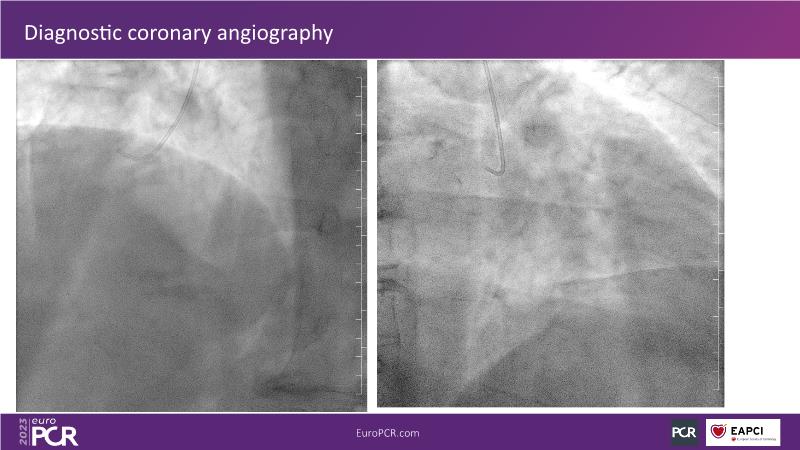

In this session focused on epicardial and microcirculatory dysfunction, discuss how to treat both a 72-year-old smoker man with HTN, diabetes, hyperlipidemia, who presented with angina and dyspnea with moderate exertion over the last months, and a 69-year-old ex-smoker man with HTN and untreated LDL 125 mg/dl who presented with chest pain of unknown origin started about 6 months ago and shortness of breath on exertion.